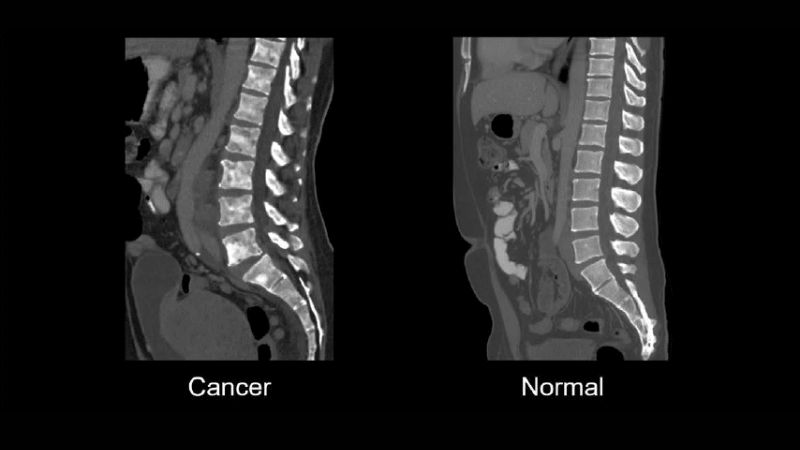

- Chụp CT (cắt lớp vi tính) cho ra hình ảnh chi tiết về xương, ống sống và các cấu trúc bên trong. Nhờ vậy, bác sĩ có thể phát hiện những “vật thể lạ” như u hoặc vết gãy một cách rõ ràng.

Người bệnh có thể được chỉ định chụp CT để phát hiện sớm các bất thường ở xương